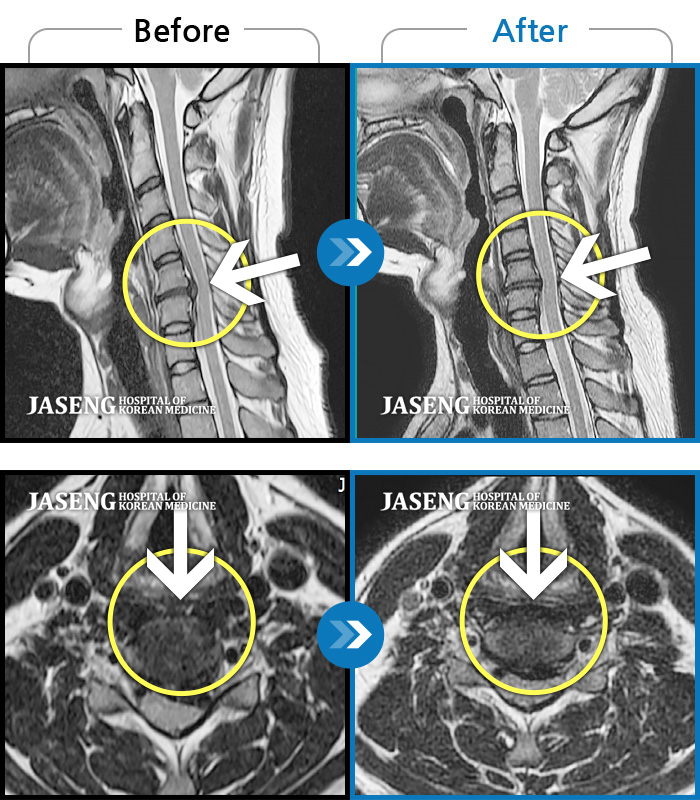

Before

After

환자에게 사전 동의를 받아 동일 조건에서 촬영되었습니다.

개인에 따라 치료 후 부작용이 발생할 수 있으니 의료진과 상담 후 치료를 진행하시기 바랍니다.

양측 허리부터 양측 골반까지 묵직하고 찌릿한 통증, 우측 하지로 이어지는 저림감

집에서 무거운 물건 들다 삐끗한 후 허리디스크가 터지고 흘러내려 극심한 통증을 호소하셨습니다